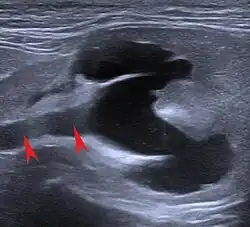

The ultrasound examination allows morphological changes in the kidneys in more detail. In addition to changes in size and shape, renal cysts, localized (focal) organ damage, water sac kidneys and urinary retention as well as tumors can also be visualized. Hardly defined (diffuse) organ changes are accompanied by changes in echogenicity, but can only rarely be assigned to defined diseases.[22] Pulsed Wave Doppler" can also be used to detect circulatory disorders.[23] Calcification (nephrocalcinosis) is also common in chronic kidney disease and can also be detected sonographically.[24]